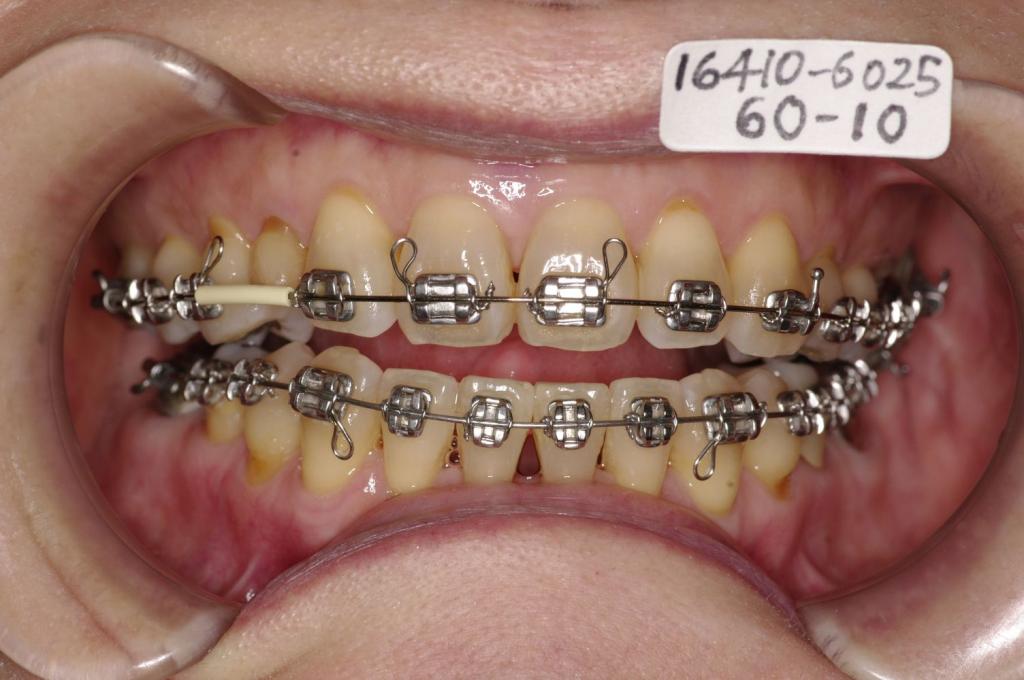

- 歯並び・咬み合わせ・八重歯・乱杭歯の矯正治療

- 上手く咬めない